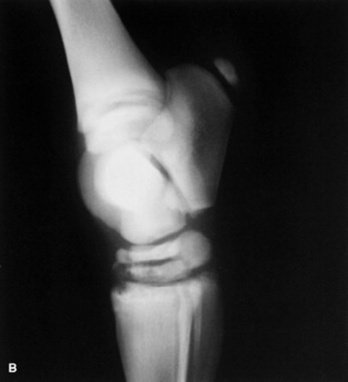

Skeletal maturity is assessed by radiographing a carpus and a tarsus for evidence of incomplete ossification (Fig. 19-1). Accelerated ossification does not appear to be a feature of foals born prematurely after exposure to chronic in utero stress. Incomplete ossification coupled with periarticular laxity predisposes the premature or dysmature foal to long-term skeletal problems. Foals with incomplete ossification and more than 30% reduction of the central and/or third tarsal bones with pinching or fragmentation of the dorsal aspects of affected bones commonly develop degenerative joint disease and have a guarded prognosis for future athletic performance. Restriction of exercise is recommended in order to minimize collapse of developing carpal or tarsal bones, but forced recumbency may predispose the foal to or exacerbate pulmonary disease. Furthermore, normal load bearing encourages ossification. Periarticular laxity predisposes the premature foal to angular limb deformities that facilitate abnormal load bearing and increase the risk of cuboidal bone crush injury of the carpus or hock. Splinting and attention to hoof care are recommended if angular limb deviation develops. In most cases flexural deformities and laxities improve over time. Dorsal splints are recommended for flexural deformities involving the fetlock, and heel extensions are helpful to foals with flexural laxity.

Fig. 19-1 A, Lateral tarsus of a 1-day-old, 305-day gestational age colt. Note the lack of ossification of the small tarsal bones. B, Lateral tarsus of the same foal as in A, at 3 weeks of age, showing irregular ossification. Without the initial radiograph, increasing ossification could have been confused with bone lysis and osteomyelitis. The foal is reported to be sound at 6 months of age.